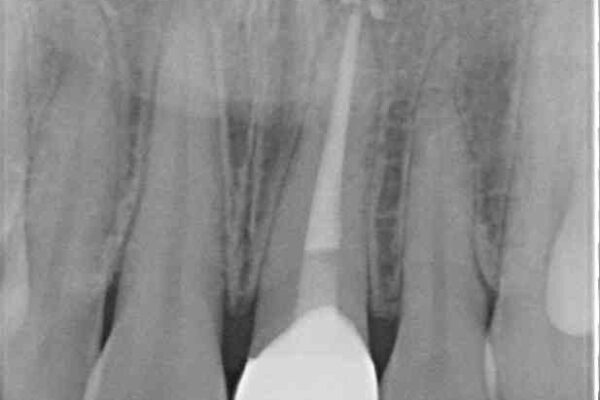

神経を取り除いたことで変色した前歯を気にして来院された患者様です。

根管治療はやり直さずに、ファイバーポストを使用した土台を植立してオールセラミッククラウンにて補綴することとしました。

治療前

• 変色した前歯をオールセラミッククラウンに 治療前画像